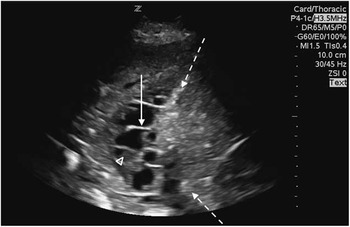

Due to the lung consolidation visible on chest x-ray, and subsequent to the decision to commence IV antbiotics and admit the patient, we performed a point-of-care ultrasound (PoCUS) of the patient’s thorax. In the right posterolateral region, we identified a complex loculated pleural fluid collection suggesting the presence of an empyema (Figures 2 and 3). The findings were reported to internal medicine and a thoracic CT was ordered for further characterization of the collection. The CT confirmed a complex loculated fluid collection consistent with an empyema (Figure 4).

Figure 2 PoCUS of the right chest, demonstrating a complex, cystic, structure. Findings in keeping with an empyema.

Figure 4 Dashed arrow: Representing the hyper echoic diaphragm. Solid arrow: Septation present within the cystic structure. Arrow head: Echogenic debris within the cystic structure, suggesting possible empyema.